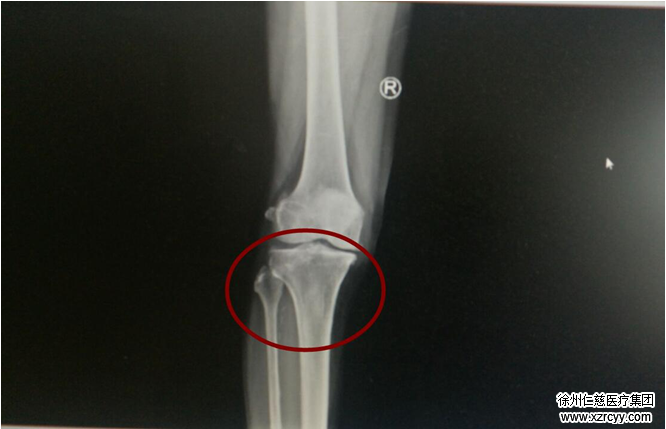

了解情况后,陈医生在门诊帮李大爷做了专科检查。指着X线片陈医生说“你看红圈这里,膝关节内侧间隙变狭窄,但关节外侧还属正常。”和徐明亮主任讨论后,陈医生告知李大爷,导致其膝关节疼痛的“坏分子”很有可能是关节力学不平衡,并建议其通过腓骨截骨手术进行治疗。